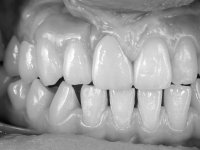

Paciente do sexo feminino, com 69 anos, não fumadora. Apresenta uma prótese combinada no maxilar superior. A porção fixa corresponde a uma ponte metalo-cerâmica de 4 elementos com os dentes 1.3/1.1 e 2.1 como pilares e o dente 1.2 como pôntico. A porção amovível corresponde a uma prótese esquelética de 5 elementos. A retenção da prótese esquelética é feita por um gancho no dente 1.4 e um “attachment tipo t” colocado no dente 2.1.

O estudo imagiológico para a colocação dos implantes, começou com a realização em laboratório de uma guia com dentes em sulfato de bário. Esta guia foi colocada em boca conjuntamente com marcas de referência coladas aos dentes, também em sulfato de bário. A guia foi estabilizada com cera mole. A TAC foi realizada com estas referências colocadas em boca. Após a realização da TAC foi feita uma impressão de arrasto em silicone. Esta impressão foi vazada a gesso em laboratório e posteriormente digitalizada. A digitalização do modelo com as referências foi sobreposta á imagem da TAC, permitindo uma planificação apurada na colocação dos implantes. Na planificação foi decidido colocar 2 implantes no local dos dentes 2.3 e 2.4 evitando-se a zona do 2.2 com pouco osso e o seio maxilar. Este estudo deu origem a uma guia cirúrgica que orientou a colocação dos implantes. Durante o período de osteo-integração a paciente utilizou a prótese removível rebasada com acondicionador de tecidos. A guia cirúrgica mostrou-se também útil na exposição dos implantes mostrando a sua localização precisa e orientando a incisão. A impressão definitiva foi realizada utilizando a técnica de moldeira aberta após eliminação do attachment. No laboratório foi confeccionada uma ponte metalo-cerâmica de 3 elementos com o elemento 2.2 em suspensão. A ponte após verificação e aprovação foi cimentada. A reabilitação apesar de pouco extensa (sem o elemento 2.6) mostrou-se capaz estetica e funcionalmente.